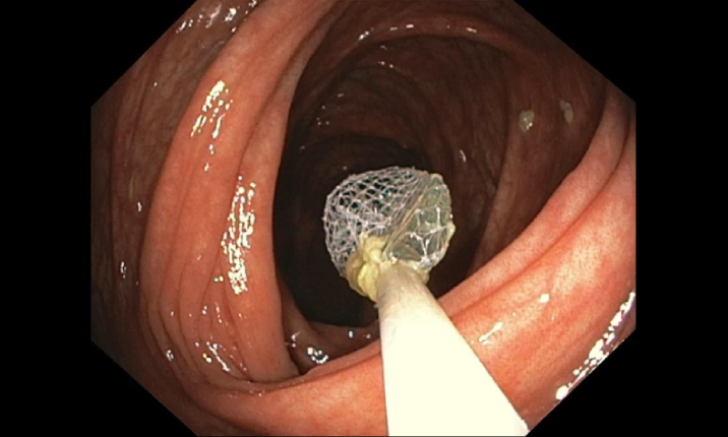

- Polypectomy

- EMR